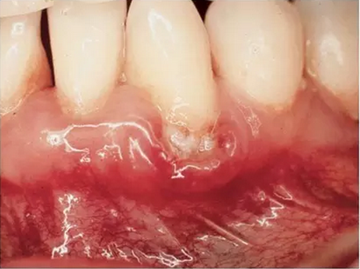

在孕期,很多女性发现她们容易患上妊娠牙龈炎——一种轻度的牙龈炎,会导致牙龈红肿和疼痛。为避免这种牙龈炎,你需要保持口腔卫生牙医可能会建议你多清洁几次牙齿。牙医可能会建议你多清洁几次牙齿。如果你发现孕期自己的口腔内有任何变化,******告诉牙医牙龈炎******及时治疗,否则会导致更严重的牙龈疾病。